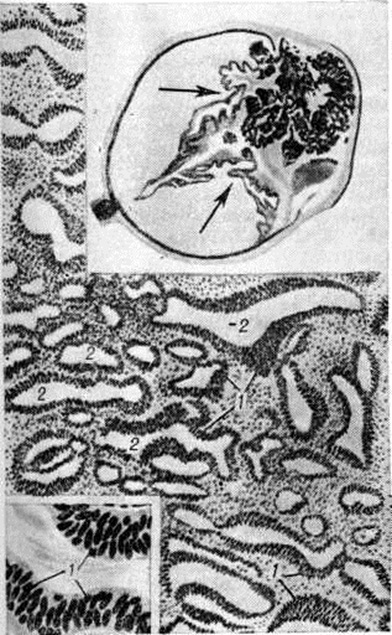

Опухоль не имеет определённой формы и представляет собой белую беспигментную массу, исходящую из плоской части реснитчатого тела. Гистологический картина напоминает строение эмбриональной сетчатки. Опухоль состоит из кубических или призматических клеток, расположенных в один или несколько рядов. Клетки формируют тяжи лентовидной формы, причудливо переплетающиеся между собой, создающие вид ажурной ткани (рисунок). У основания тяжей имеется тонкая мембрана, между складками их — нежная волокнистая ткань, встречаются митозы. Иногда в опухоли встречаются островки гиалинового хряща, что послужило основанием для некоторых авторов трактовать её как тератоневрому. В большинстве описанных случаев метастазов при Диктиома не наблюдалось.